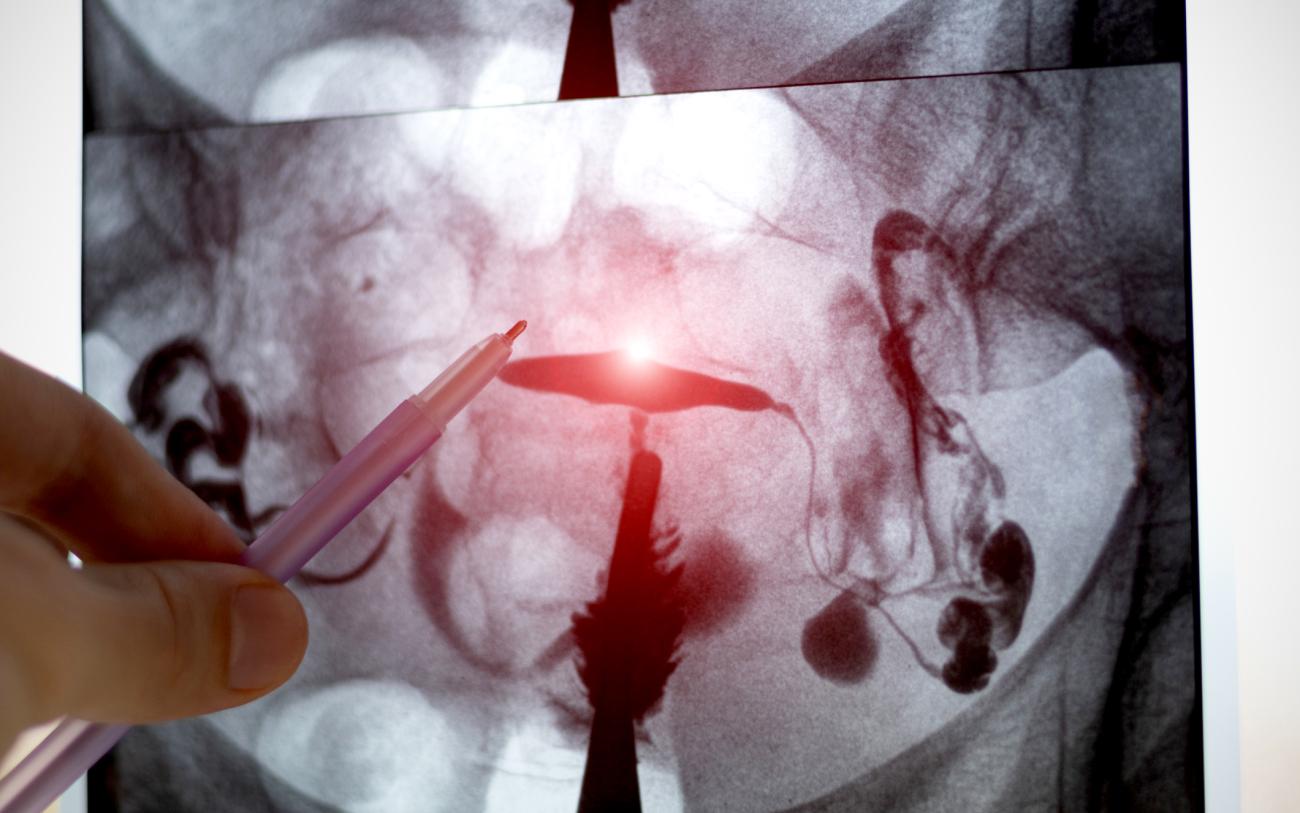

A: Ovarian cancer is a type of gynecologic cancer that affects organs within the female reproductive system. This includes the ovaries, which produce eggs and hormones, and the fallopian tubes, which allow eggs to travel from the ovaries to uterus. Some ovarian cancer cell types begin directly in the ovaries, but the most common type — called high-grade serous cancer — actually starts in the fallopian tubes.

Ovarian/fallopian tube cancer is unique in that it has no vaccine, no simple screening test and no single symptom of early disease. It causes more deaths than all other gynecologic cancers combined, mainly because these tumours often spread within the abdomen before they are discovered.